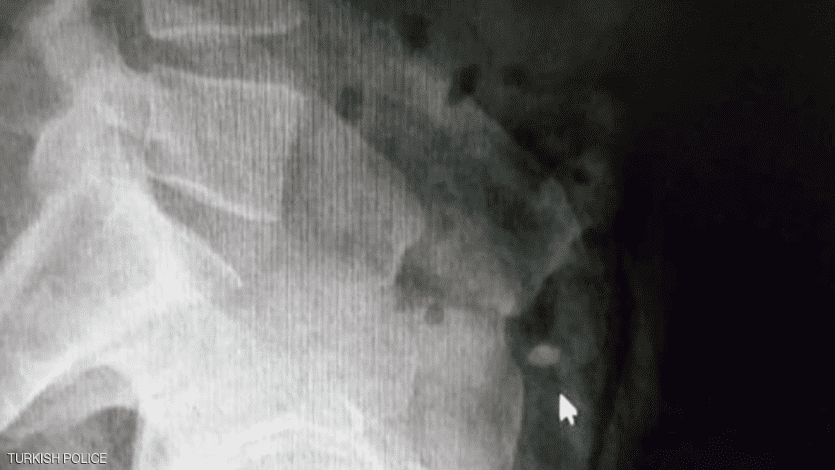

وأمرت الشرطة بنقل السارق إلى المستشفى، من أجل إجراء عملية جراحية للعثور على الخاتم، ما لم يعد الأيرلندي الخاتم بـ"الطريقة الطبيعية".

وتابعت وسائل إعلام تركية "رحلة" الخاتم، لحظة بلحظة لمدة يومين كان خلالها اللص ينتظر في المستشفى بعدما تناول أدوية تسهّل الإخراج، وذلك تحت حراسة الشرطة.

وقد قفز مرارا في المستشفى لتحريك الخاتم في أحشائه لمدة 36 ساعة، لكن جهوده كانت بلا جدوى، وبعد ذلك لجأت السلطات إلى استخراج الألماس عبر عملية جراحية.